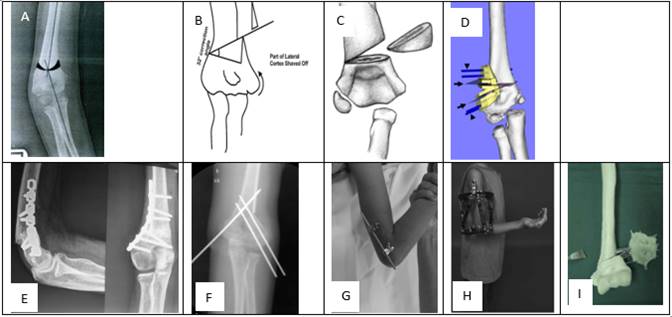

Son múltiples los criterios de evaluación clínicos y radiográficos encontrados en la bibliografía para de medir las deformidades a nivel del codo (Imagen 1). Oppenheim en 1984 describe el humeral-elbow-wrist angle (HEW) para evaluar los resultados postoperatorios en las osteotomías del humero distal 15. Recientemente este ángulo fue validado como una medida fiable de la alineación en el plano coronal del humero y del antebrazo. El mismo se traza mediante una primera línea a nivel de la diáfisis humeral y una segunda línea perpendicular a dos puntos medios transversales que cruzan el antebrazo. La línea proximal se traza al nivel de la tuberosidad radial y la distal en la curvatura del radial. Un valor negativo indica varo, mientras que un valor positivo indica valgo 16.

El ángulo de carga es un ángulo formado entre el eje longitudinal del humero y una segunda línea que pasa a través del eje longitudinal del cubito. La línea diafisaria cubital pasa por el centro de dos líneas transversas. La línea proximal se traza a nivel del olecranon y la distal se traza a nivel de la tuberosidad bicipital 17.

El ángulo de Baumann se calcula trazando una línea a través de la diáfisis humeral y una segunda línea a través de la fisis del cóndilo. Tiene una baja fiabilidad dada la dificultad de identificar la fisis en pacientes mayores 18.

El Índice de Prominencia Lateral (LCPI) descrito por Wong et at valora la prominencia del cóndilo trazando una línea medio humeral longitudinal, midiendo de esta forma la diferencia del ancho del lado medial y lateral. El resultado se expresa en porcentaje. (Imagen 1) 19